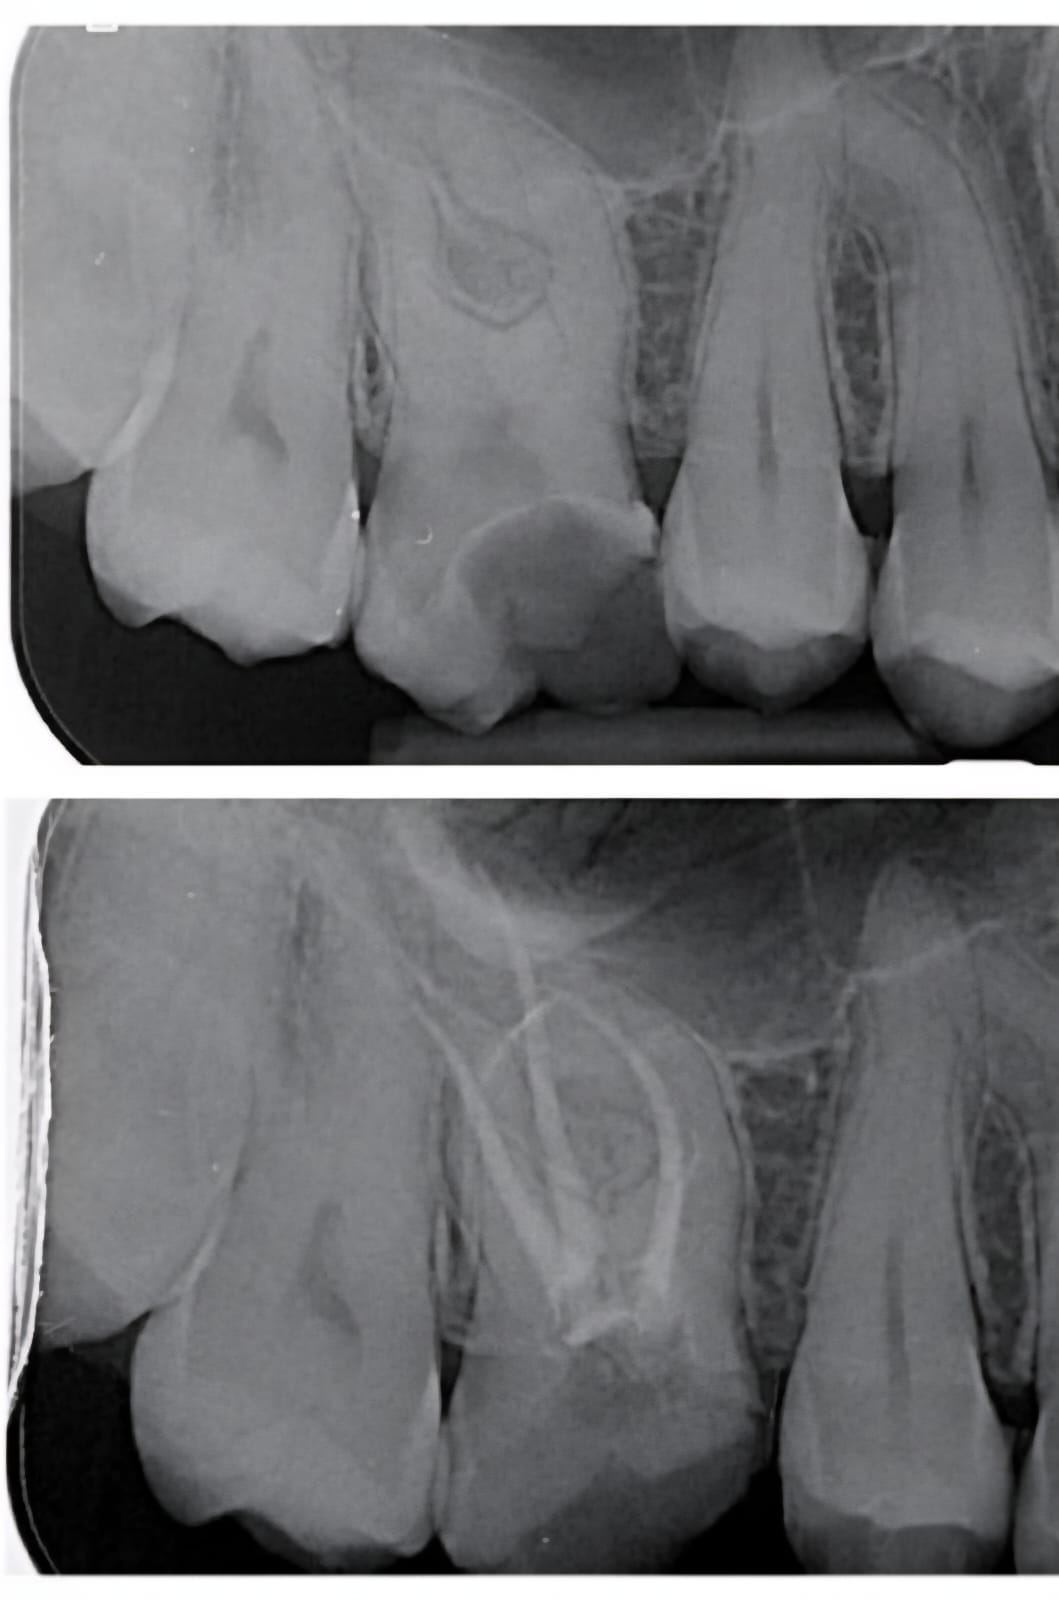

Folosind microscop endodontic, tehnologie digitală și instrumente rotative moderne, asigurăm curățarea perfectă a canalelor radiculare și o vindecare rapidă, fără disconfort.

Microscop endodontic pentru precizie totală

Fiecare canal este tratat sub mărire de până la 25x, pentru curățare completă și rezultate durabile. Utilizarea microscopului reduce semnificativ riscul apariției infecțiilor recurente

Permite vizualizarea detaliată a canalelor dentare și tratarea completă a celor mai fine ramificații. Fără complicații, fără infecții ascunse.

Consultația și radiografia digitală

Se realizează o radiografie pentru a evalua structura dintelui și extinderea infecției. Stabilim planul exact de tratament.